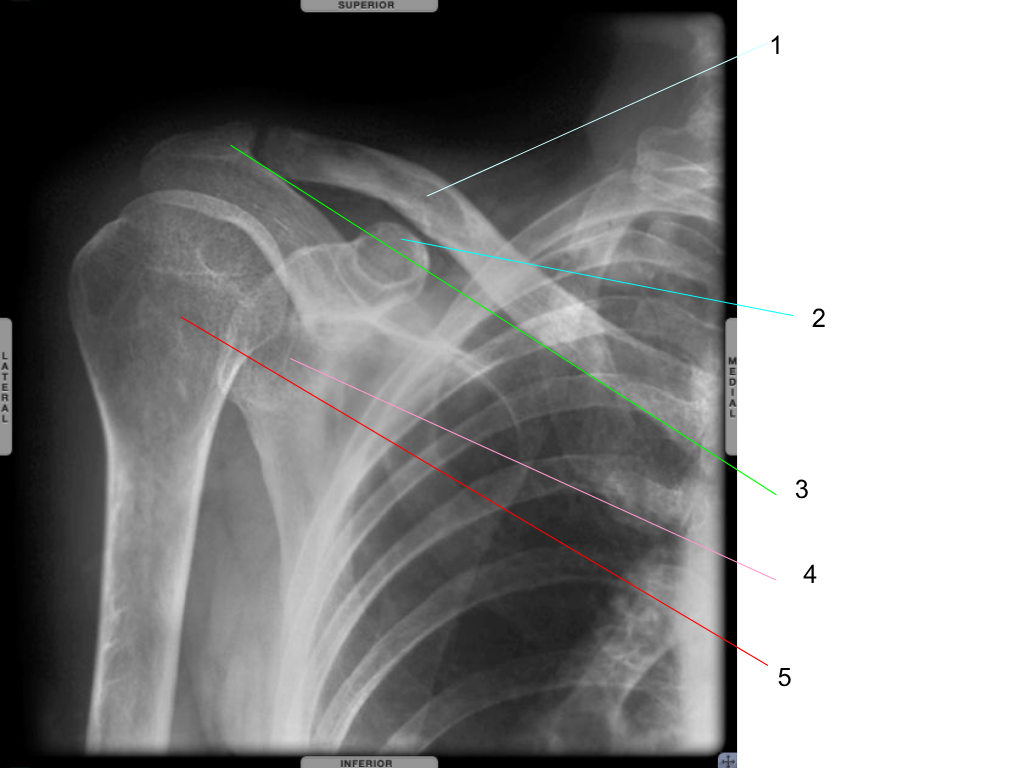

clavicle

what is #1 pointing at?

coracoid process

what is #2 pointing at?

acromion

what is #3 pointing at?

glenoid fossa

what is #4 pointing at?

humeral head

what is #5 pointing at?